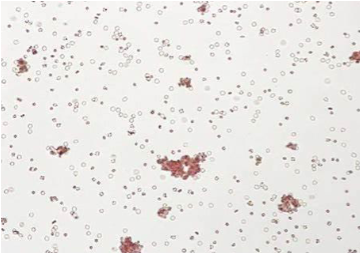

explain the theory behind saline replacements

patients’ samples with abnormal serum protein concentrations, reversed albumin-to-globulin ratio, or plasma expanders can aggregate reagent red blood cells and can mimic agglutination

saline replacement frees cells in the case of true rouleaux formation

true agglutination: RBCs remain clumped after addition of saline → positive

rouleaux: RBC aggregates disperse into free cells with the addition of saline → negative